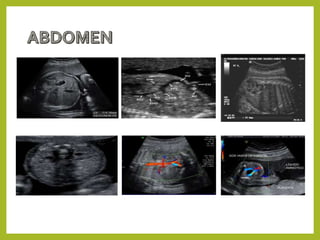

Abdomen

• Circunferencia abdominal.

• Pared anterior del abdomen.

• Vejiga y riñones.

• Relación entre CA y renal.

• Medición de la circunferencia abdominal (CA).

• Identificación del estómago, de la pared anterior del abdomen, la vejiga y los riñones.

• Con la medición exacta de la CA, se obtendrá una estimación precisa del peso fetal (evalúa el crecimiento fetal).

• El estómago aparece como estructura redonda anecogénica situada en la parte superior izquierda del abdomen.

• La forma y el volumen del estómago son muy variables según el grado de llenado y la peristalsis.

• Si el estómago no se visualiza, el examen debe repetirse más tarde.

• Evaluación del tamaño y ecogenicidad de los riñones.

• Identificación de los vasos renales puede ser útil en la evaluación de las anomalías congénitas de los riñones.

• El ultrasonido tiene un papel indirecto en la evaluación de la función renal, de la medición de líquido amniótico, la

presencia de orina en la vejiga, la relación entre la circunferencia abdominal y renal y el grosor cortical de los riñones.